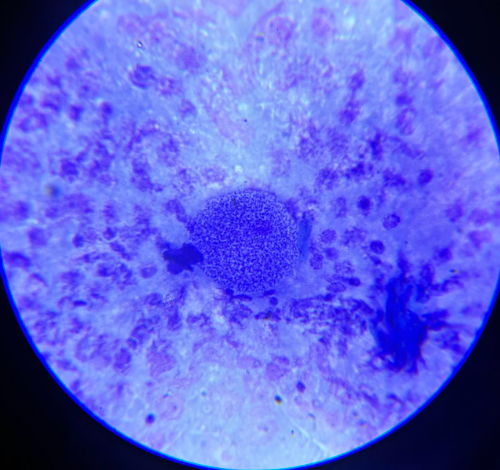

echinococcus granulosus protoskoleksy